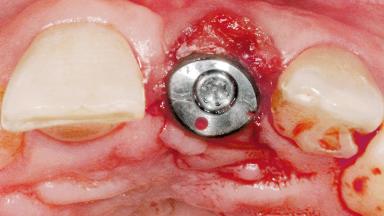

# of Implants 1

Type of Implants Two-Piece

Attachment Two-Piece

SAC Level Advanced

Defining Characteristics One missing tooth to be replaced by an implant-borne prosthesis